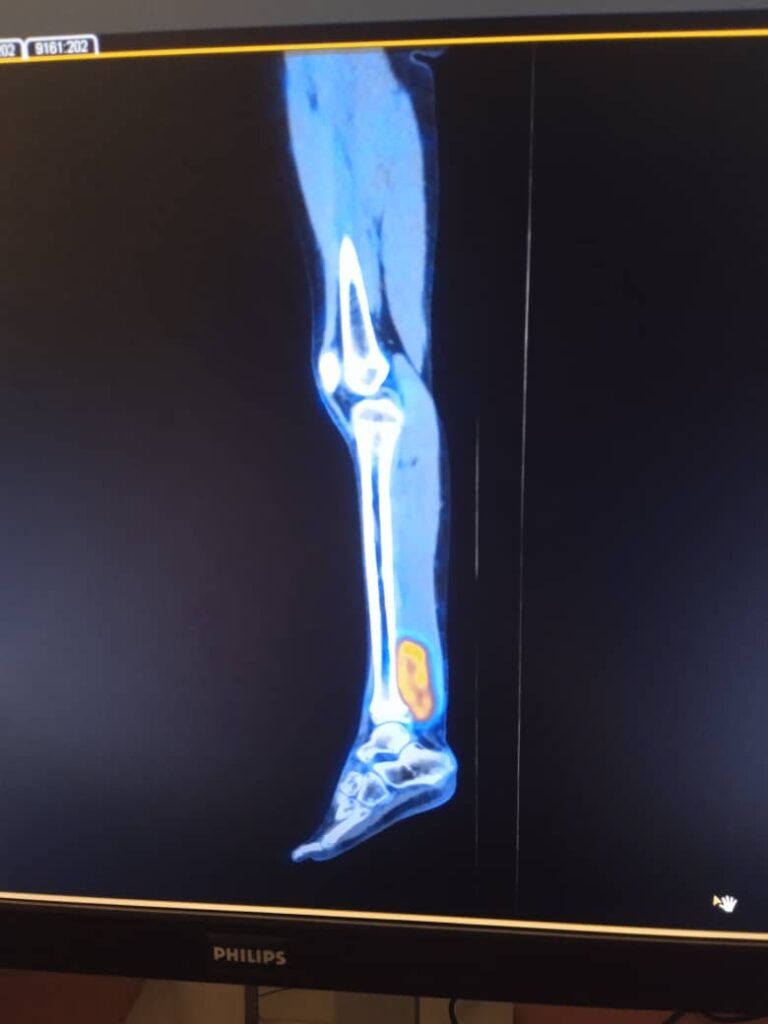

Las fotos que publicamos muestran a la niña en el hospital, donde fue sometida a una intervención quirúrgica.

Sofía está internada en el Hospital Pediátrico Provincial Docente “Pepe Portilla”, de la occidental provincia de Pinar del Río.